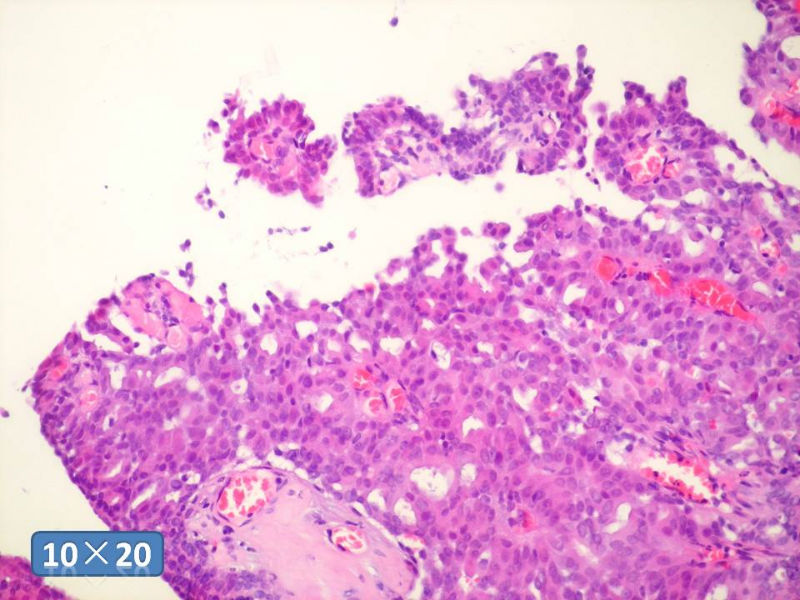

只能说是乳头状瘤

是不是导管内

乳头状瘤 and 导管内乳头状瘤 are the same; Benign lesion.

After you work up and you still cannot be sure it is benign , atypical or maignant lesion, you can call 乳头状lesion.

If this is excisonal case, you should figure out the nature of the papillary lesion.

我的意思就是提醒大家 在不是很确定的情况下 尽量少给自己套枷锁